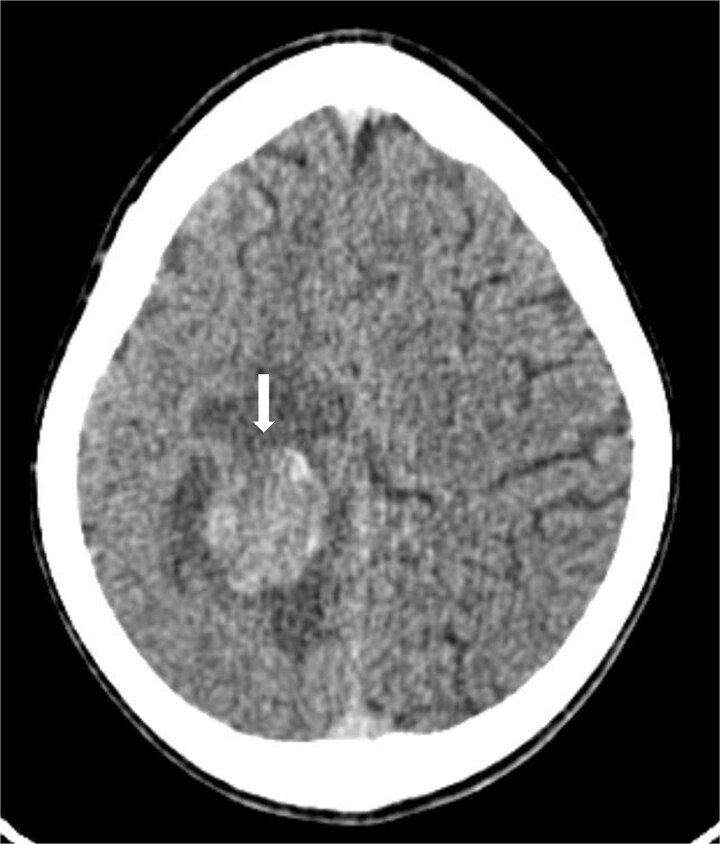

骨肉瘤是儿童和青少年中最常见的恶性骨肿瘤,以长骨为主,常发生肺转移。脑转移是罕见的,发生在1.8%至5.6%的病例中,出血性转移非常罕见,文献中只有少数病例记录。我们报告的情况下,一个16岁的女孩谁提出急性头痛和癫痫发作。影像显示出出血性脑和肺转移,活检证实为原发性股骨骨肉瘤。本病例是一种罕见的骨肉瘤,并突出了其侵袭性转移行为。

Osteosarcoma is the most common malignant bone tumor in children and adolescents, with a predilection for long bones and frequent pulmonary metastases. Brain metastases are rare, occurring in 1.8% to 5.6% of cases, and hemorrhagic ones are exceptionally uncommon, with only a few cases documented in the literature. We report the case of a 16-year-old girl who presented with acute headache and seizures. Imaging revealed hemorrhagic brain and pulmonary metastases, and biopsy confirmed a primary femoral osteosarcoma. This case represents an exceptionally rare presentation of osteosarcoma and highlights its aggressive metastatic behavior.